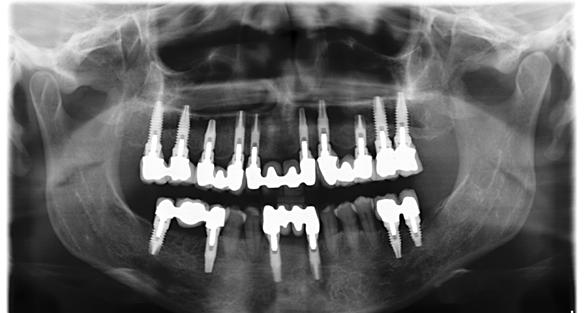

Figura 1. Radiografía inicial de la paciente. Se observa edentulismo total superior, a excepción del molar del primer cuadrante, indicado para exodoncia. En la mandíbula se aprecia pérdida ósea horizontal generalizada secundaria a la evolución de la enfermedad periodontal.

En la radiografía inicial (Figura 1) se observa la pieza 17 con pérdida ósea significativa, así como una reabsorción ósea homogénea a lo largo de todo el arco superior. En la arcada inferior se aprecia pérdida ósea horizontal generalizada y defectos localizados, como una lesión en cuña en la pieza 46. Ante esta situación, se decide realizar la exodoncia del molar remanente del

En el arco superior se planifica una rehabilitación cementada por tramos, que en ese contexto representaba la mejor alternativa en términos de estética y estanqueidad, mediante pilares específicos para fresado. Para ello se programan 10 implantes. En una primera fase se realiza la carga inmediata

del sector anterior y la carga definitiva de los implantes mandibulares mediante una prótesis de resina atornillada (Figura 3).

Seis meses después se cargan los implantes de los sectores posteriores con una prótesis atornillada sobre transepiteliales de larga duración en metal-resina, lo que permite generar una carga controlada y favorecer la adecuada conformación de los tejidos periimplantarios (Figura 4).

Figura 12. Radiografía final con la prótesis cementada en posición.

La paciente continúa bajo seguimiento periodontal. A los 5 años se observa estabilidad clínica del tratamiento (Figuras 22–24), sin recesiones gingivales ni pérdida ósea asociada en las imágenes clínicas y radiográficas.

El mantenimiento periodontal y la implicación de la paciente en las medidas de autocuidado se mantuvieron de forma constante durante 23 años (Figura 25). La ortopantomografía realizada en una de las visitas de control mostró estabilidad completa de los implantes, sin signos radiográficos de pérdida ósea patológica.

Figura 21. Radiografía con la rehabilitación finalizada.

Figura 24. Radiografía a los 5 años que evidencia estabilidad ósea periimplantaria y periodontal.

25. Radiografía a los 25 años con mantenimiento del nivel óseo en implantes y dientes remanentes.